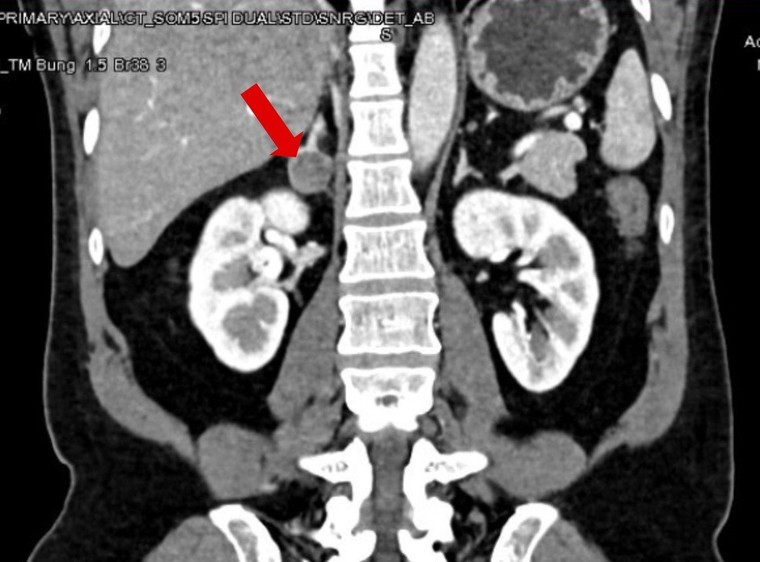

Kết quả cho thấy, bệnh nhân có một khối u nhỏ với kích thước 25 mm ở tuyến thượng thận phải. Vì là khối u rất nhỏ nên rất khó phát hiện, nhưng đây chính là nguyên nhân khiến người bệnh tăng huyết áp bất kiểm soát và chứng hạ kali suốt thời gian qua, bác sĩ Duy nhận định.

![]() |

Khối u ở tuyến thượng thận phải gây ra tình trạng huyết áp tăng cao, khó thở kéo dài ở người bệnh. Ảnh: BVĐK Tâm Anh cung cấp. |

Ngay sau đó một cuộc hội chẩn liên khoa diễn ra giữa các bác sĩ Khoa Nội tiết và Trung tâm Tiết niệu Thận học, các bác sĩ thống nhất phương án phẫu thuật cắt tuyến thượng thận phải cùng khối u bằng phương pháp nội soi 3D. “Khối u có kích thước tuy nhỏ nhưng lại gây ra hệ lụy lớn đến sức khỏe cho người bệnh”, bác sĩ Nguyễn Hoàng Đức, người trực tiếp phẫu thuật cho người bệnh, nhận định.